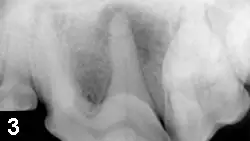

Figure 1 (above) Typical appearance of a complicated crown fracture in the maxillary left 4th premolar

Fractured teeth (Figure 1) are common in dogs and cats1,2 and may be a result of trauma or may be identified by a client who notices that a pet’s tooth suddenly looks different. In some cases, the patient may have difficulty eating or acutely develop facial swelling (Figure 2). It is critical that treatment be recommended for all fractured teeth (vs a watch-and-wait approach); many patients still eat and drink despite a fractured tooth, and because an abscess may not be obvious, periapical pathology can only be evaluated via dental radiographs (Figure 3). Facial swelling and draining tracts signal an abscessed tooth’s end stage, in which infection and discomfort have likely been present but were not clinically apparent.2 Uncomplicated crown fractures with no pulp exposure should also be evaluated with radiographs; if there is no periapical pathology, dental sealants can protect exposed dentin tubules and prevent contamination and eventual pulp involvement.